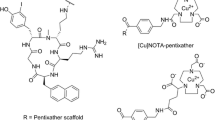

Recently, we have developed N-[11C]methyl-AMD3465 as a radiotracer for PET imaging of CXCR4 receptors [12]. The aim of this study is to investigate various methods for quantification of CXCR4 availability using N-[11C]methyl-AMD3465 PET in immune-competent tumor-bearing rats. We also investigated whether this approach can be applied to measure CXCR4 receptor occupancy of the drug Plerixafor® (AMD3100 8HCl). To date, no report has been published on the estimation of CXCR4 receptor occupancy by PET.

Hartimath SV, van Waarde A, Dierckx RAJO, de Vries EFJ (2014) Evaluation of N-[11C] methyl-AMD3465 as a PET tracer for imaging of CXCR4 receptor expression in a C6 glioma tumor model. Mol Pharm 11:3810–3817

Hartimath SV, Domanska UM, Walenkamp AME et al (2013) [99m Tc] O 2-AMD3100 as a SPECT tracer for CXCR4 receptor imaging. Nucl Med Biol 40:507–517

Jacobson O, Weiss ID, Szajek L et al (2009) 64Cu-AMD3100—a novel imaging agent for targeting chemokine receptor CXCR4. Bioorg Med Chem 17:1486–1493